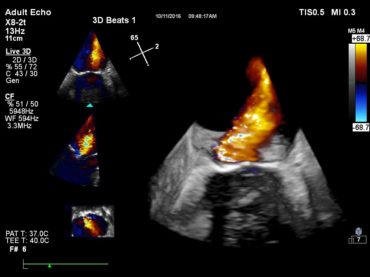

Condividendo il DNA cardiologico del sistema Premium leader Epiq CVx, Affiniti CVx è capace di esaminare un'ampia gamma di pazienti cardiopatici grazie alla sua versatilità e all’alta qualità di immagini. Affiniti CVx è in grado di catturare immagini nitide e straordinarie con trasduttori avanzati tra cui il trasduttore X8-2t TEE, il trasduttore X5-1 e la sonda S5-1 a cristallo singolo.

Esame transtoracico ottimizzato con un migliore imaging in pazienti tecnicamente difficili (TDP), sfruttando le funzionalità e gli strumenti clinici avanzati tra cui Live 3D TEE e AutoStrain LV per una quantificazione del ventricolo sinistro della deformazione 2D rapida e riproducibile.